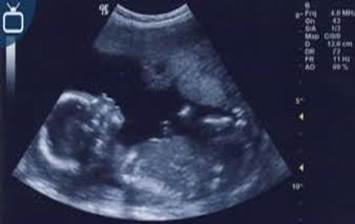

Bu hafta bebeğinizin boyu 19 cm, ağırlığı ise 190 gramdır.

Bu haftada bebeğinizin orta kulak kemiklerinin ve sinirlerinin gelişimi, annenin sesini veya dış ortamdan gelen şiddetli sesleri duyacak kadar gelişmiştir. Artan sıvı miktarı ve kıkırdak dokusunun kemikleşme sürecinin hızlanması ile bebeğinizin hareketleri artmıştır. Baş parmağını emebilir, yüz mimikleri artmıştır. Kız bebeklerde yumurtanın öncüsü yapıyı içeren foliküller oluşmaya başlar.